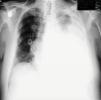

A un hombre de 62 años de edad se le diagnosticó MM (Ig G-kappa) en estadio IIIA en junio de 2010. Se le trató con 2 ciclos de bortezomib y, a continuación, se le realizó un trasplante autógeno de células madre en septiembre de 2010. Para mantenimiento se le trató con ciclofosfamida a una dosis de 50mg/día. Se presentó con dolor en el pecho en agosto de 2012 y se le detectó una masa palpable en el hemitórax izquierdo. La radiografía simple mostró múltiples fracturas costales y el PET-TAC reveló una masa expansiva de 8×9cm ubicada en el hemitórax izquierdo a la altura de las costillas 9.ª y 10.ª (valor de captación estandarizado máximo 15,5). Los resultados de las pruebas de laboratorio fueron: hemoglobina 14,1g/dl, leucocitos 5×109/L, plaquetas 242×109/L, creatinina 0,8mg/dl, ácido úrico 6mg/dl, calcio 10,7mg/dl, proteína total 7,4g/dl, albúmina 4,9g/dl, globulina 2,5g/dl, kappa 217mg/dl y microglobulina β-2 3.668ng/ml. La electroforesis de proteínas séricas fue normal. La detección por FISH de 17p13, 1 (gen p53) fue negativa. La biopsia de médula ósea mostró infiltración de células plasmáticas CD138 (+) y kappa (+). Se le trató con lenalidomid-dexametasona y, tras 2 ciclos de tratamiento, se detectó un derrame pleural en el hemitórax izquierdo en noviembre de 2012 (fig. 1). Se realizó toracocentesis, que reveló exudado con 6g/dl de proteína. El examen citológico mostró pequeños linfocitos, leucocitos polimorfonucleares, células mesoteliales y células plasmáticas atípicas positivas a CD138 e Ig G-kappa. La tinción inmunohistoquímica frente a HHV-8 fue negativa y los cultivos bacterianos y de micobacterias fueron negativos. Se añadió tratamiento con bortezomib, pero el paciente falleció por insuficiencia respiratoria 2 meses tras el diagnóstico de afectación pleural.

El derrame mielomatoso maligno aparece por una infiltración de la pleura causada por la proliferación anormal de células plasmáticas de un plasmocitoma extramedular de la pared torácica, de los pulmones o de los huesos. Los criterios de diagnóstico del derrame pleural mielomatoso son: hallazgo de una proteína monoclonal por electroforesis del líquido pleural, detección de células plasmáticas atípicas en el líquido pleural y confirmación histológica por biopsia pleural4. La afectación de la cavidad pleural tiene mal pronóstico y se administró quimioterapia sistémica (interferones, bortezomib, talidomida), radioterapia, trasplante autógeno de células madre e inyección directa de agentes quimioterápicos en la cavidad pleural. Ha habido muy pocos casos de derrame pleural maligno en los que bortezomib haya sido eficaz, pero la infiltración pleural resulta fatal, con una mediana de supervivencia de 1,5-3 meses. Por lo tanto, en el mieloma con afectación de las cavidades pleurales, se pueden indicar los regímenes de quimioterapia más agresivos.